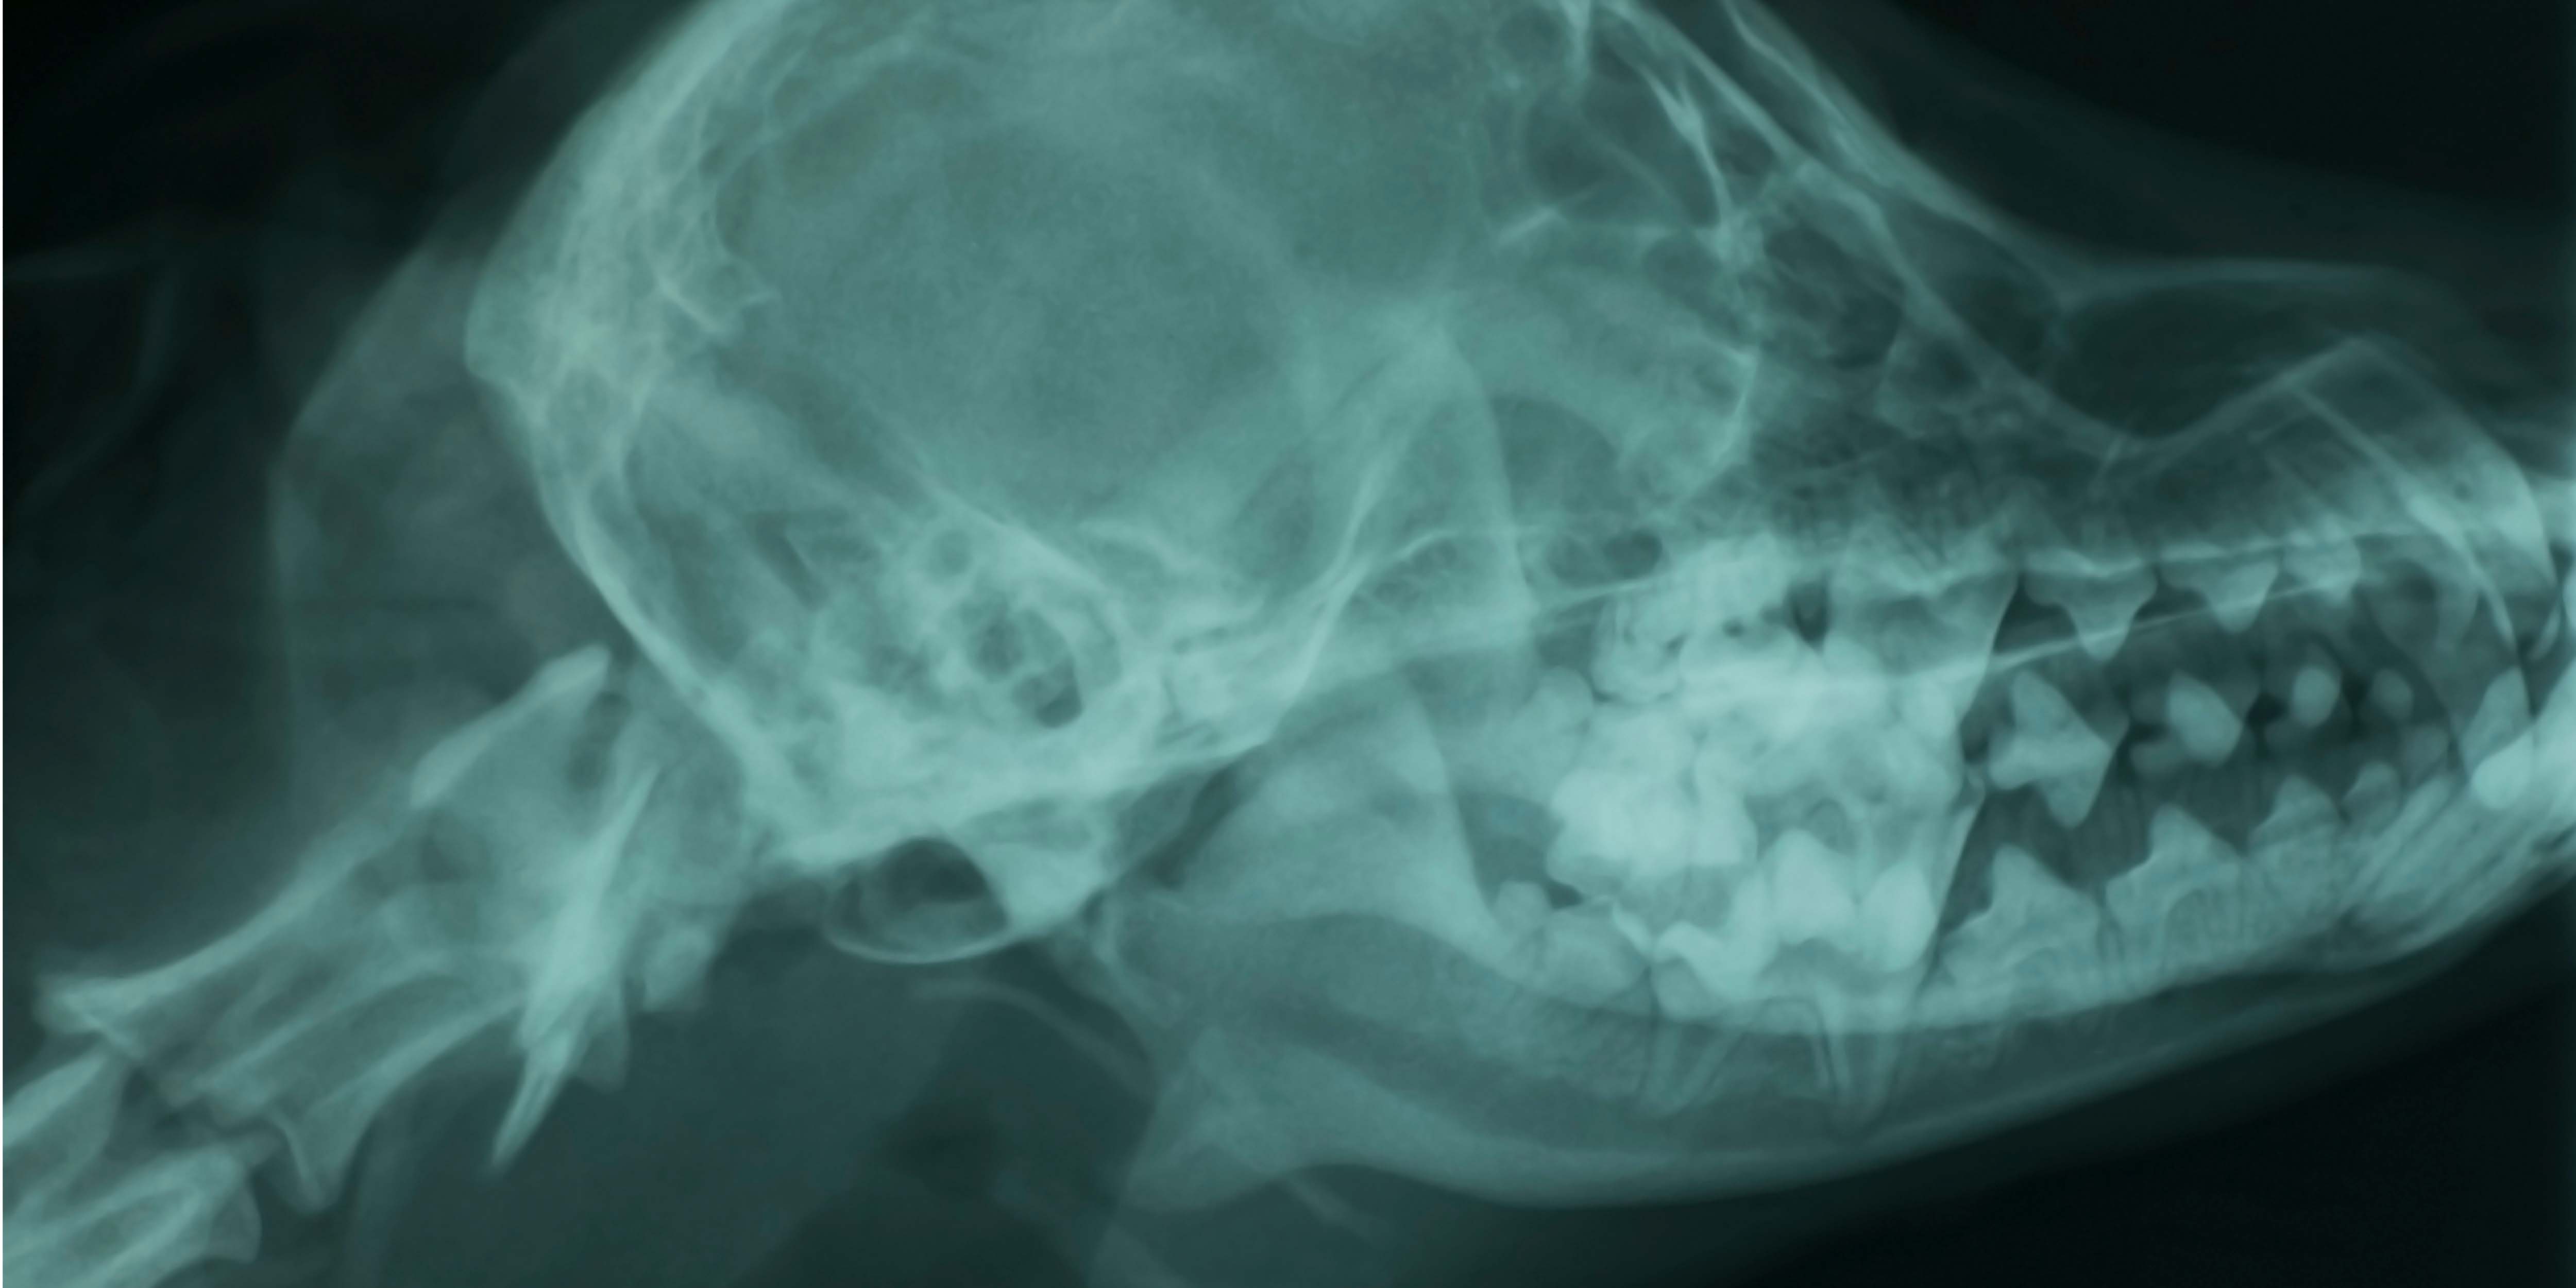

This webinar offers veterinarians a practical overview of intraoral dental radiography, covering its indications, interpretation, and role in clinical decision-making. It highlights how radiographs can reveal subgingival pathology invisible during oral examinations, improving diagnosis and client communication. We'll review normal anatomy and common radiographic findings, such as bone loss, periapical lesions, root pathology, and tooth resorption in cats and dogs. Practical tips are provided for using radiographs in treatment planning, estimating procedural complexity, and confirming extractions through pre- and post-procedural imaging. The presentation concludes with recommendations for case documentation, ongoing monitoring, and client education to improve care quality and build trust.